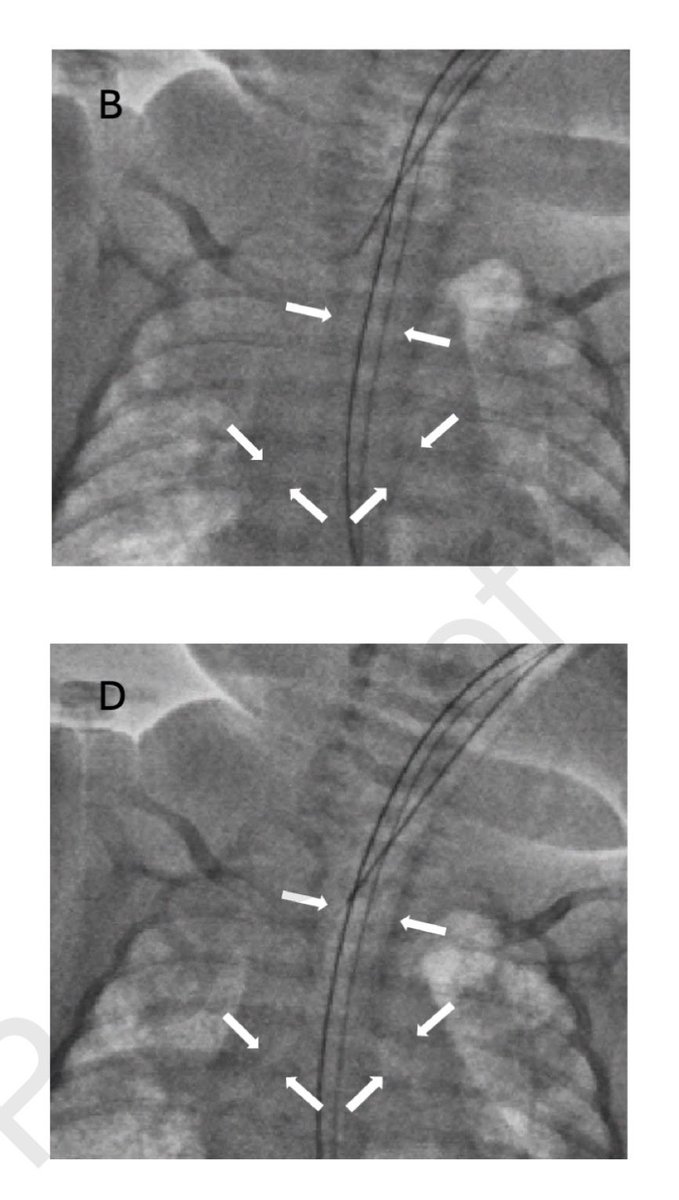

👀 Looking for new ways to better prognosticate in ARF? 🫁 Ever heard of CT findings: *️⃣ superimposed pressure or *️⃣ gas-to-tissue ratio? @ERezoagli et al show us they can be helpful for spontaneously breathing patients, in #journal_CHESTCritCare: chestcc.org/article/S2949-…